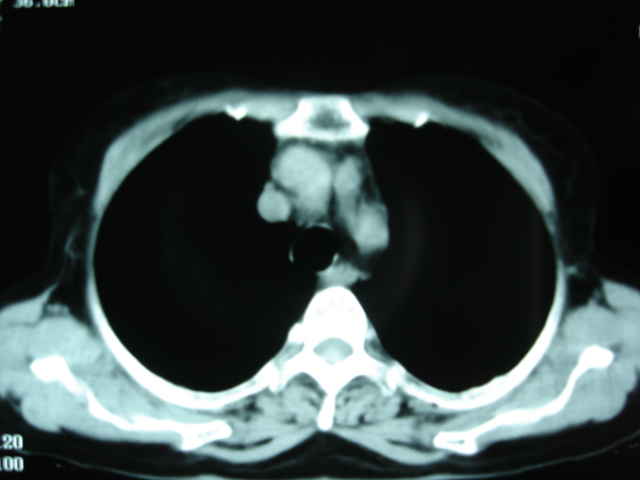

以下是引用卜一在2009-9-7 19:51:00的发言:[br][br] 1 左侧胸内甲状腺占位-多考虑甲状腺腺瘤! 2、左肺门占位-建议增强扫描以便明确性质。 3 慢支并感染! [br]

以下是引用shibing在2009-9-7 20:40:00的发言:[br]左侧胸内甲状腺占位-多考虑甲状腺腺瘤! 2、左肺门占位-建议增强扫描以便明确性质。 3 慢支并感染! [br]